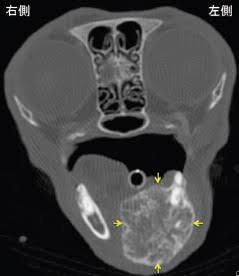

・CT検査

私のお勧めとしては、CT検査を行い骨への浸潤や腫瘤の大きさ、血管等への浸潤をしっかり確認した上で切除病理を実施します。経験から全身麻酔をかけるにあたり、腫瘤が大きく挿管が困難な場合がある為、注意して行ってください。